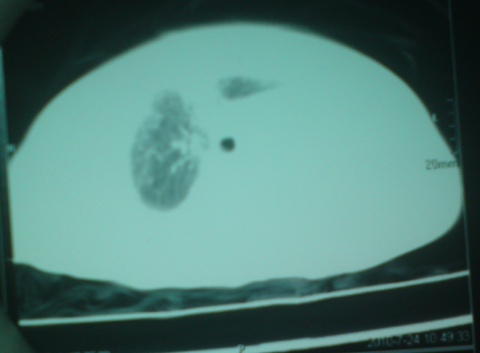

以下是引用liaoqiang在2010-7-26 13:10:00的发言:[br]左侧主支气管未显示,左肺体积明显缩小。右肺体积大。肋间隙不窄。考虑左肺不发育伴右肺代偿性肺气肿、纵隔疝。

以下是引用江广1996在2010-7-26 10:34:00的发言:[br]因为胸廓对称,肋间隙基本正常,故考虑为先天性左肺不发育。[br]如为异物,也会有临床病史。另,这与双胞胎有什么关系,另一个情况怎样?有无检查过?